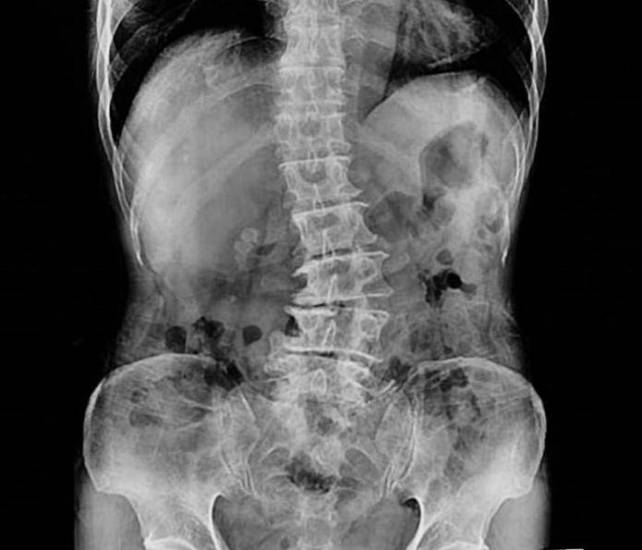

В 1965 году В. Д. Чаклин рентгенологически выделил 4 степени деформации позвоночника при сколиозе:

- 1-я степень — 5-10 градусов;

- 2-я степень — 11-30;

- 3-я степень — 31-60;

- 4-я степень — более 61 градуса.

- При 1-й степени в положении стоя отмечается слабость мышечного корсета спины и брюшной стенки, разный уровень плеч, углы лопаток располагаются на разных уровнях, асимметрия треугольников талии. В грудном отделе заметно искривление, в поясничном — на противоположной стороне мышечное уплотнение, которое также видно при наклоне корпуса вперед. На рентгеновском снимке отсутствуют признаки ротации позвонков. Таз расположен в горизонтальной плоскости. В положении лежа на спине отмечается слабость мышц брюшного пресса.

- При 2-й степени визуально определяется S-образное искривление позвоночника. Имеются ротации грудных позвонков, происходит деформация грудной клетки. Проба с наклоном показывает выступание ребер с одной стороны или мышц поясницы. Прогрессирование идет, пока ребенок растет.

- При 3-й степени определяется выраженная деформация скелета. Отчетливо виден реберный горб и перекос таза. Линия плеч совпадает с линией таза. Сдавливается венозное сплетение позвоночника. Могут быть нарушения со стороны дыхательной системы.

- При 4-й степени наблюдается тяжелая степень деформации всего туловища. Прекращается рост, нарушается взаимоотношение внутренних органов. Сдавливание спинного мозга приводит к развитию парезов. На рентгенограмме выявляются клиновидные позвонки.